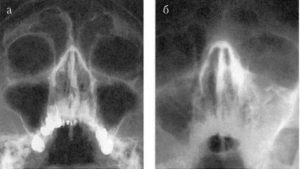

По характеру протекания выделяют: острый и хронический с односторонним поражением правой или левой гайморовых пазух; двусторонний с воспалением слизистых в обеих лакунах. Обычно процесс начинается с односторонней инфильтрации слизистой оболочки верхнечелюстных пазух.

Для двустороннего катарального синусита характерны признаки серозного воспаления. Кроме сильного отека отмечается болезненность при пальпации пазух и в области нижних век. Заболевание сопровождается истечением густого секрета. В отличие от одностороннего переносится тяжелее из-за большей зоны поражения и активного выброса токсинов в кровь.

Взрослых специалист направляет на рентгеноскопию и ультразвуковое исследование. При недостатке информации назначает пункцию. Детям и беременным рентген противопоказан. Вместо него используют метод диафаноскопии, изучая области гайморовых пазух с помощью лампы Геринга.

- рентген-исследование пазух;

В организме человека есть две гайморовы пазухи, расположенные симметрично. Воспаление может поражать любую из них, а также обе полости одновременно. В зависимости от локализации патологического процесса выделяют следующие формы катарального синусита:

- Односторонний. Типичные признаки наблюдаются с левой или справой стороны носа. Встречается в 80% случаев, хорошо поддается лечению и диагностике.

- Двухсторонний. Поражает одновременно обе верхнечелюстные пазухи. Это усиливает выраженность симптоматики, усложняет процесс лечения.

Локализацию болезни проще всего обнаружить на рентгеновском снимке. Патология отображается на нем в виде темных пятен различного объема.